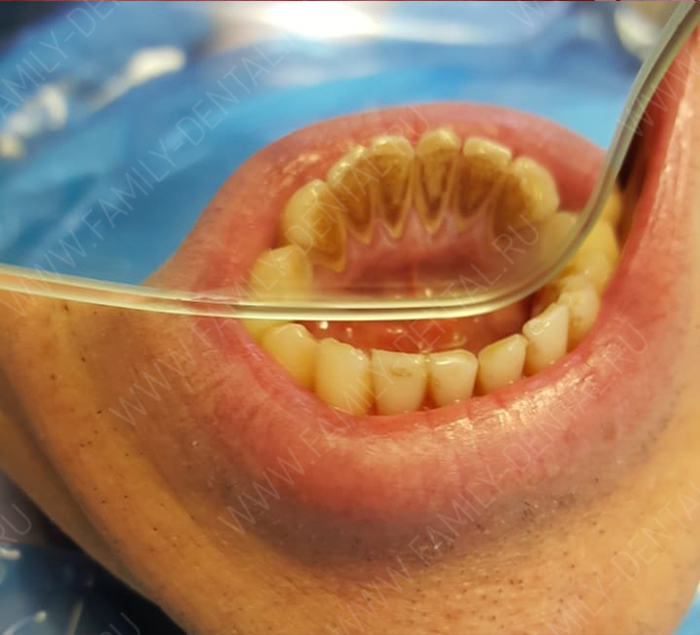

Кариес – распространенная проблема, затрагивающая людей всех возрастов, и подростки не являются исключением. Переходный возраст – это время гормональных изменений, изменений в рационе и часто не самого дисциплинированного подхода к гигиене полости рта. Все это создает благоприятную среду для развития кариеса, который может протекать более агрессивно, чем у взрослых. В этой статье мы подробно разберем особенности лечения кариеса у подростков, а также рассмотрим эффективные методы профилактики.

Появление кариеса у подростков обусловлено целым рядом факторов. Во-первых, это гормональные изменения, которые влияют на состав слюны и ее защитные свойства. Снижение буферной емкости слюны делает зубы более уязвимыми к кислотному воздействию бактерий. Во-вторых, изменение пищевых привычек – увеличение потребления сладких газированных напитков, шоколада, конфет – создает благоприятную среду для размножения кариесогенных бактерий.

Нельзя забывать и о недостаточной гигиене полости рта. В подростковом возрасте многие пренебрегают регулярной чисткой зубов, не используют зубную нить и ополаскиватели, что приводит к накоплению зубного налета и образованию кариозных полостей.

Ортодонтическое лечение, ношение брекетов также увеличивает риск развития кариеса, так как брекеты затрудняют тщательную очистку зубов.